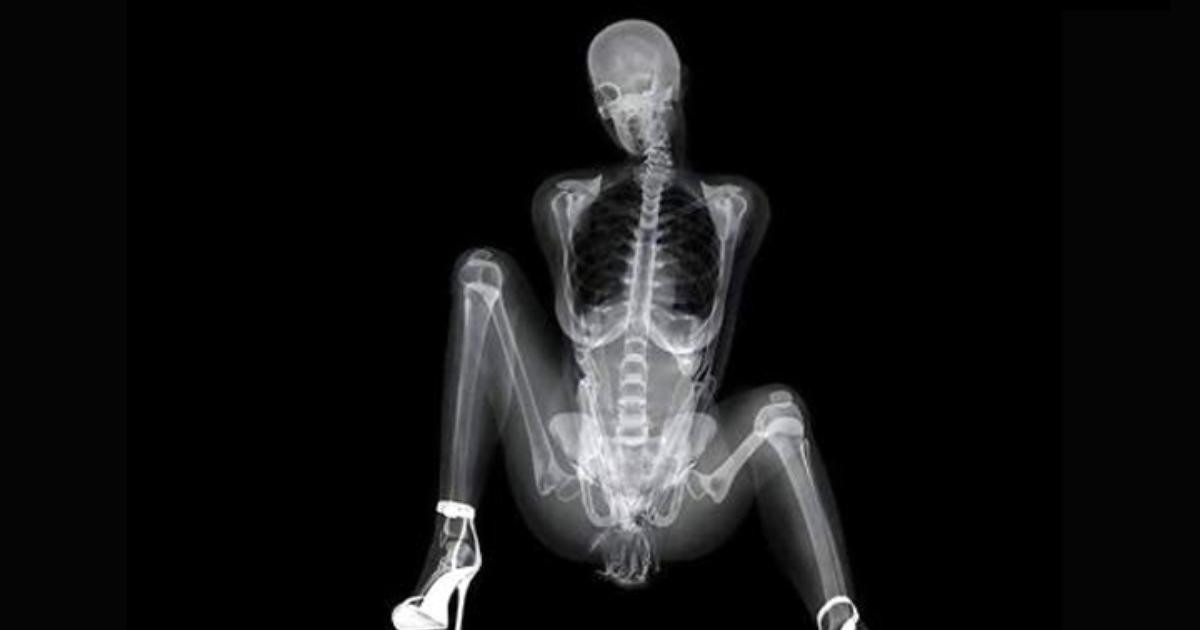

PIRLANTA RÖNTGEN FİLMİNDE GÖRÜLDÜ

Röntgen filmi çekilince kadının bağırsaklarında bir taş görülmesi üzerine Xulian, gerçeği itiraf etti ve pırlantayı çaldığını söyledi.